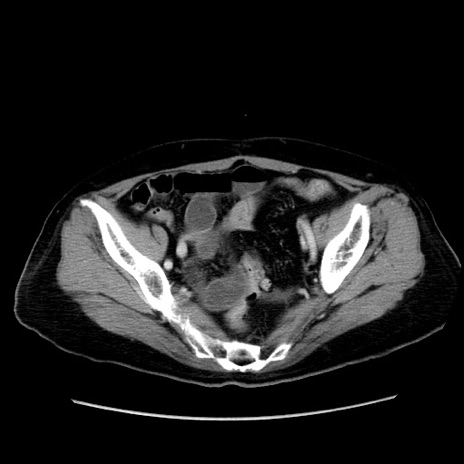

症例19(横断像)

【症例】80歳代女性

【主訴】下腹部痛

【現病歴】約8時間前より下腹部痛の出現あり、救急外来受診。

【既往歴】両側付属器切除

【身体所見】意識清明、下腹部正中に手術痕あり、その部位に一致して圧痛と反跳痛あり。腸蠕動音は亢進。

【データ】WBC 9300、CRP 0.15